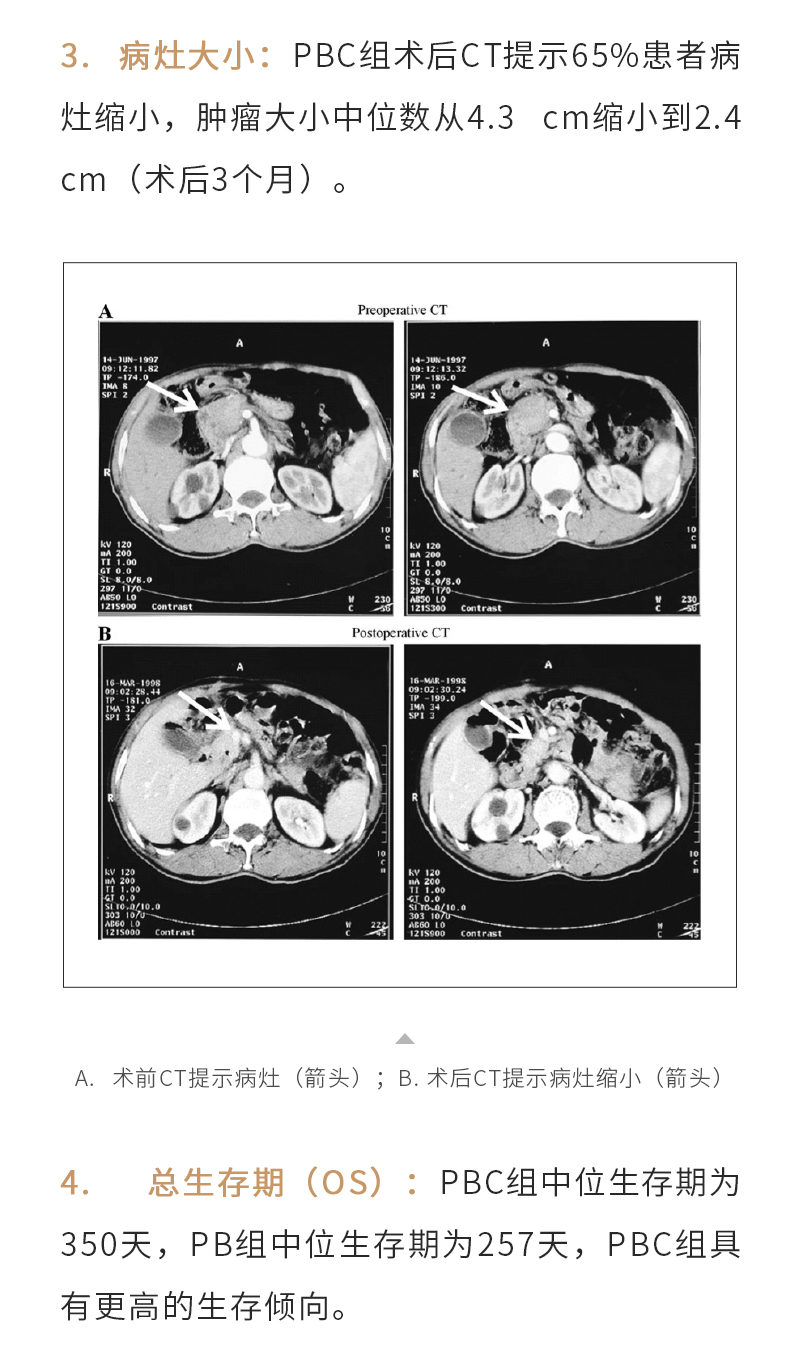

上一页:冷冻消融肺结节——【海杰亚科研资讯】第266期

下一页:微波消融治疗肝癌——【海杰亚科研资讯】第264期